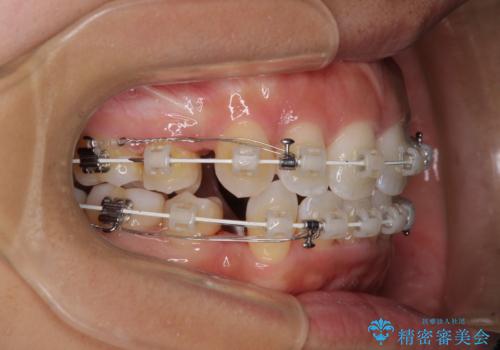

- 審美装置

上下顎ともに前突した歯列であったので、上下ともに左右の第1小臼歯4本を抜歯し、ワイヤー装置にて矯正治療を行うこととしました。

抜歯スペースに前歯を移動させることで歯の突出感が改善され、非常に唇が閉じやすい仕上がりとなりました。